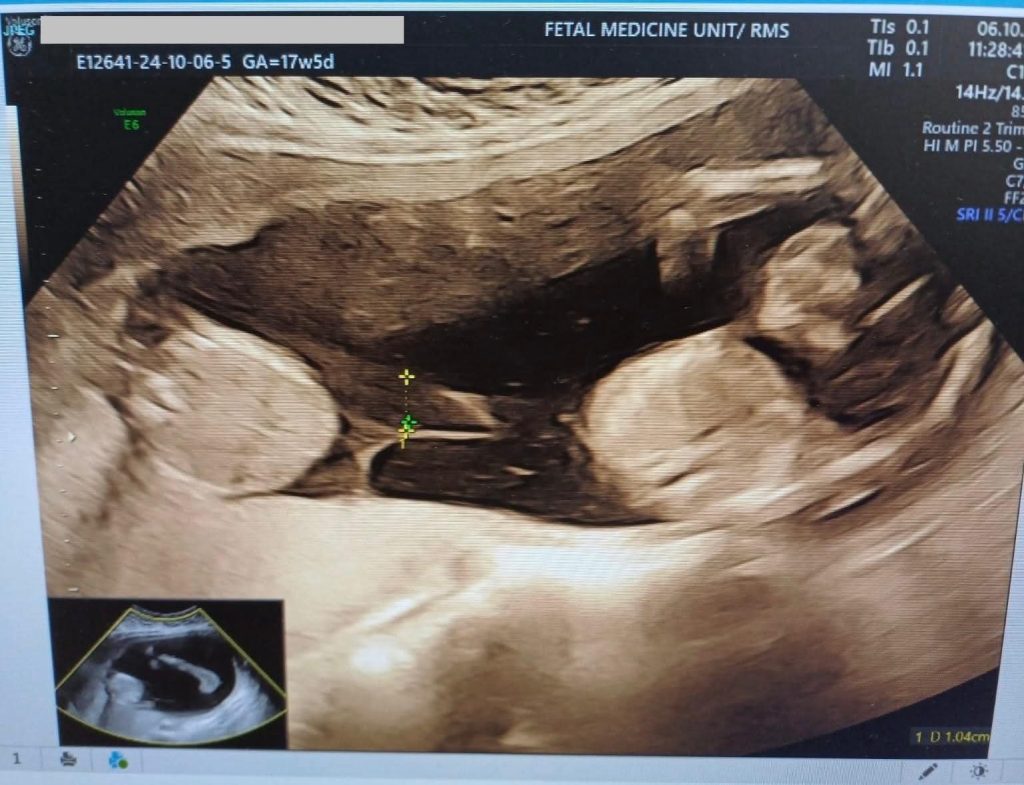

المرفأ- في إنجاز طبي جديد يُضاف إلى سجل التميز، نجح فريق طب الجنين في دائرة النسائية والتوليد بالخدمات الطبية الملكية في إجراء عملية دقيقة لفصل المشيمة الأحادية باستخدام تقنية الليزر (Fetoscopic Laser Ablation).

وأوضح الفريق الطبي أن العملية تكللت بالنجاح، حيث استمر الحمل بشكل طبيعي حتى الأسبوع 37 و4 أيام، دون تسجيل أي مضاعفات تُذكر، في مؤشر واضح على دقة الإجراء وكفاءة الفريق القائم عليه.